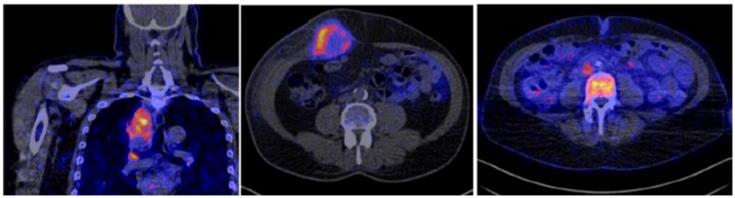

Figure 1

(A) Mechanism of uptake of 18F-ARAG: Reproduced from Levi J et al. CCR (doi:10.1158/0008-5472.CAN-19-0267). (B) Patient with head and neck carcinoma. PET/CT imaging with 18F-FDG and 18F-ARAG shows prominent uptake in the lesions in larynx; uptake is also noted in 18F-ARAG scan with heterogenous uptake. (Courtesy: Drs. Colevas, Sunwoo, and Davidzon, Stanford University) (Reprinted with permission from Elsevier, Pandit-Taskar N, Postow MA. Immune-Directed Molecular Imaging Biomarkers. Semin Nucl Med. 2020 Nov;50(6):584-603. doi: 10.1053/j.semnuclmed.2020.06.005. Epub 2020 Jul 15. PMID: 33059826.)

To overcome this issue, 9-(β-D-Arabinofuranosyl) guanine (AraG), a non-catabolizible imaging agent, was developed. As a guanosine analog, it can be phosphorylated by dCK and, consequently, trapped intracellularly in T cells in vivo without any toxicity [10, 11], therefore serving as an ideal targeted small molecule PET imaging tracer (Figure 1). In a murine model of colorectal cancer, two days post-administration of anti-PD-1 treatment, responder mice showed a significantly higher 18F-AraG PET signal in their tumors relative to a non-responder mice, indicating 18F-AraG PET was able to successfully predict the response to programmed death-1 (PD-1) blockade [11]. In patients, 18F-AraG preferentially accumulates in activated CD8+ T cells with about 7 times higher uptake in activated T cells as compared to murine cells [10]. Currently, four phase I (NCT04524195, NCT04052412, NCT04678440, NCT04186988) and two phase II (NCT04726215, NCT04260256) human studies are underway to study biodistribution and kinetics in patients with non-small cell lung cancer (NSCLC) treated with checkpoint blockade.